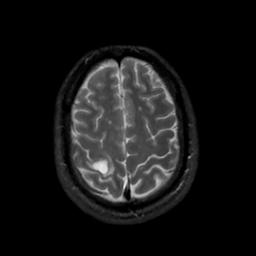

MR Study #7, March 24, 1991 -- Slice #40